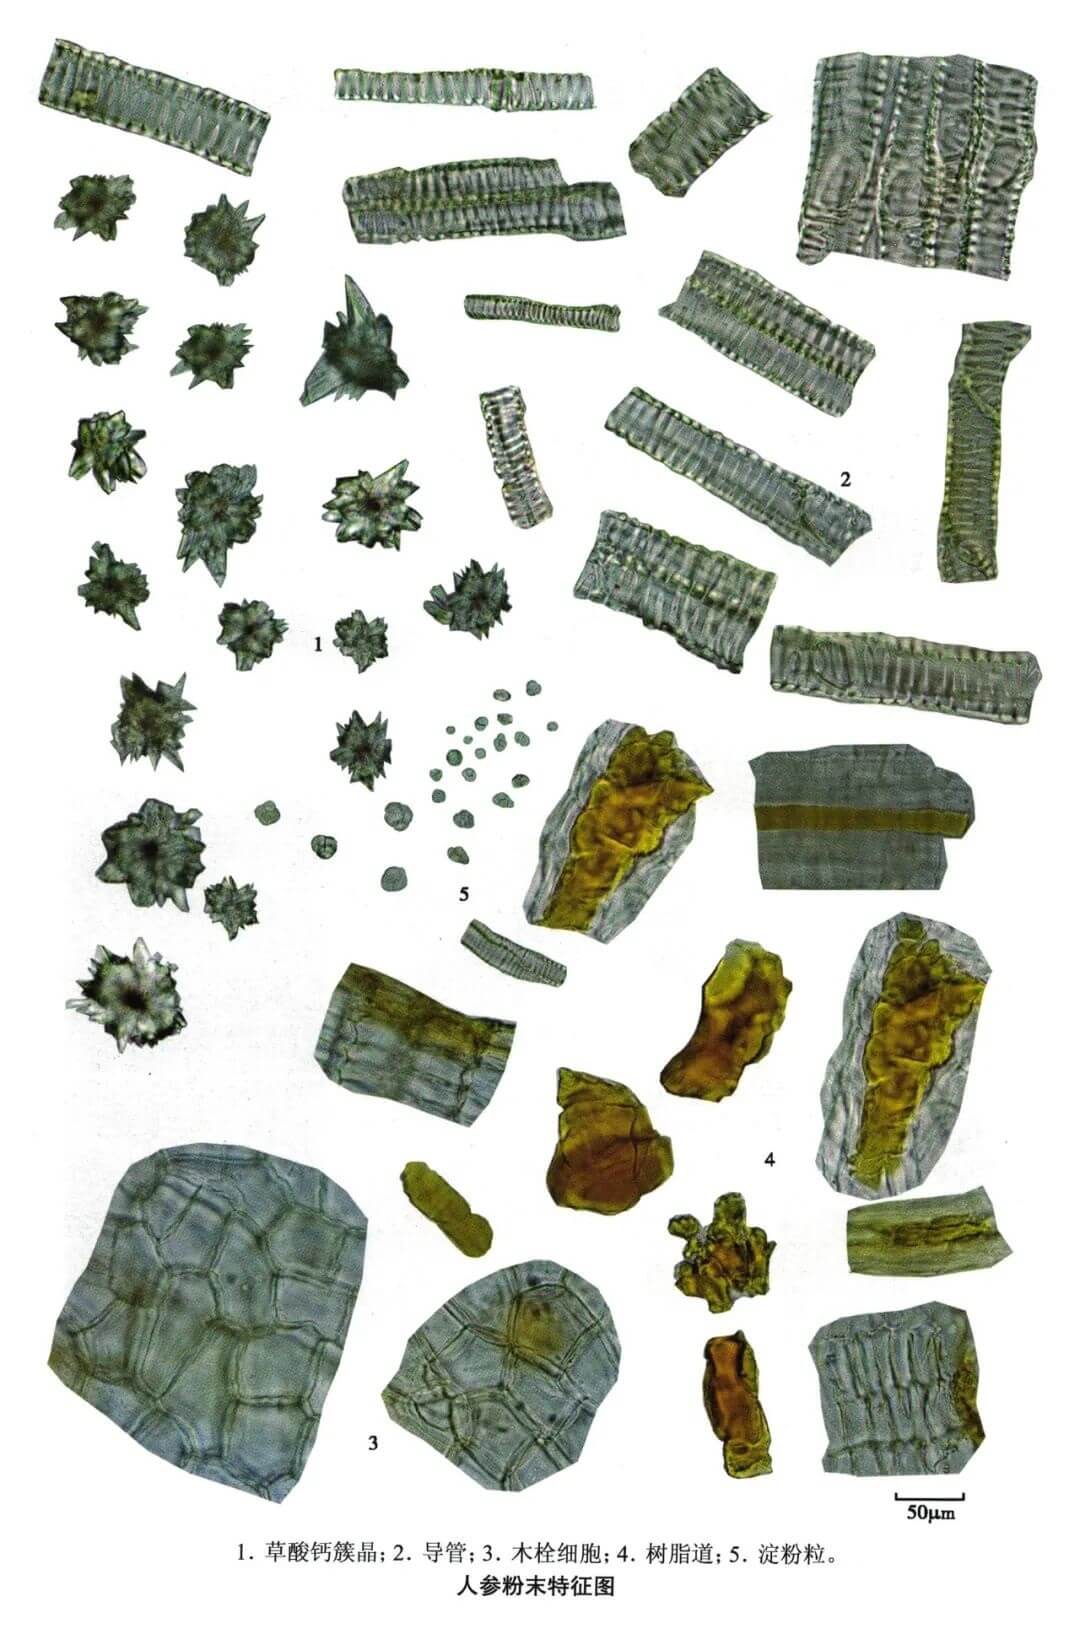

人参

| 人参 |

|---|

| 【参考标准】 《中国药典》2020年版一部 |

| 【显微鉴别】 粉末淡黄白色。树脂道碎片易见,含黄色块状分泌物。草酸钙簇晶直径20~68μm,棱角锐尖。木栓细胞表面观类方形或多角形,壁细波状弯曲。网纹导管和梯纹导管直径 10~56μm。淀粉粒甚多,单粒类球形、半圆形或不规则多角形,直径4~20μm,脐点点状或裂缝状;复粒由2~6分粒组成。 |

| 【显微重点】 草酸钙簇晶及其棱角锐尖;树脂道。 |

| 【图谱来源】 《中药成方制剂显微图典》 |